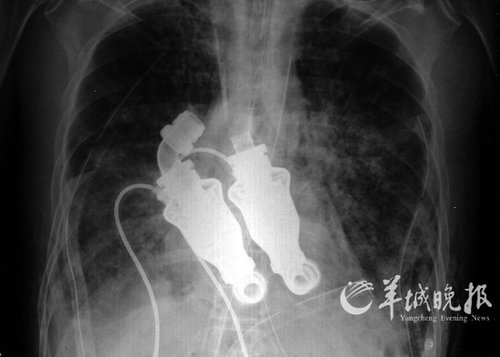

騰訊科技訊 據2011年6月16日消息,美國科學家發明了一種沒有心跳的人工心臟。德克薩斯心臟研究所的醫生已經對其進行了測試。這種新型人工心臟利用旋轉渦輪機使血液保持流動,而不需要再模仿心臟的跳動來向身體提供連續的血液。發明者Billy Cohn和Bud Frazier稱,這種人工心臟已經在動物身上進行測試并完成了一個成功的試驗,目前沒有出現不良影響。研究所動物研究實驗室里一頭8個月大的小牛是首批接受該心臟移植的受體之一。兩位發明者說:“如果你用聽診器聽它的胸部,不會聽到心跳;如果你檢查它的動脈,也不會有脈搏;你給它做心電圖的話,只會看見一條平線。”